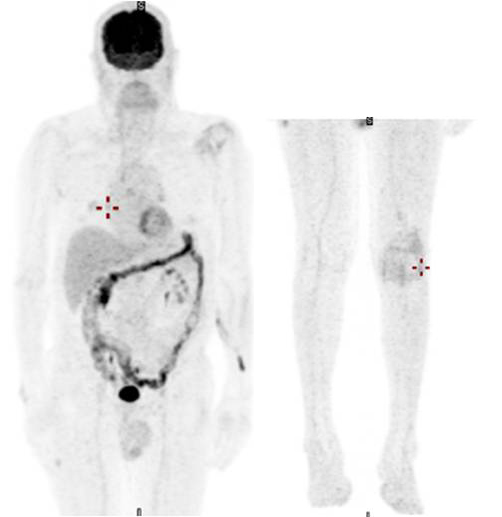

張義芳表示,病患是從去年5月開始進行每3周一次的免疫治療,共執行9次療程,原先只能臥床,進步到可以自由行走,腫瘤範圍也逐漸縮小至只剩下小手指,體力與氣色都看得到顯著的進步。

黑色素癌第四期的患者經由正子攝影,原先癌細胞擴散全身多處(上圖),接受免疫療法之後,癌細胞明顯清除(下圖)。圖/馬偕醫院提供